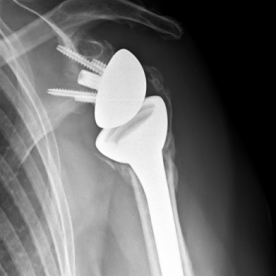

Röntgenbilder